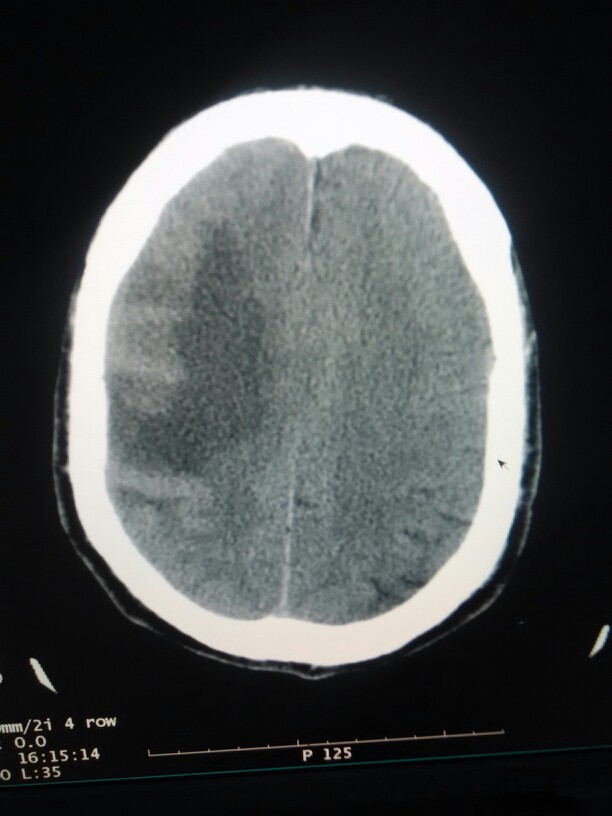

男性患者,60岁。无明显诱因出现,面瘫10天余,伴头痛。来我院做颅脑ct扫描,平扫显示。右侧额颞叶,可见片状等密度为主混杂密度影,CT值21,到31.2不等,周围大片状低密度环绕,周围脑组织明显受压,三脑室受压变形移位,中线结构左移。大家讨论一下考虑是什么样的占位性病变。